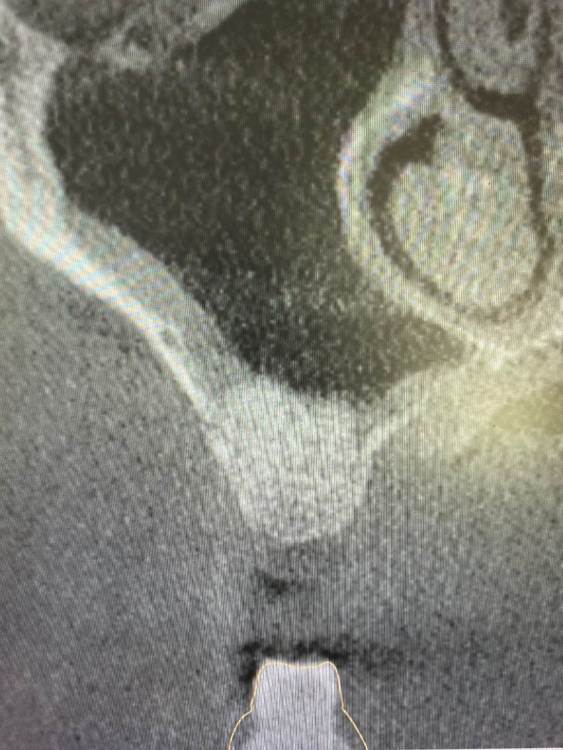

kamranchick Опубликовано 5 августа, 2021 Поделиться Опубликовано 5 августа, 2021 Приветствую, первый раз сталкиваюсь с подобной ситуаций стандартная ситуация, ОСЛ с использованием чистого апатос кортикал, ожидание 5 месяцев,заживление без осложнений сегодня начинаю сверление, и один сплошной фиброз какой прогноз коллеги? стоит ждать чуда? прилагаю снимки Ссылка на комментарий

Irouil Опубликовано 14 августа, 2021 Поделиться Опубликовано 14 августа, 2021 А как именно себя фиброз проявил? может быть отслойка по каудальной стенке получилась не «чистой» - по КТ «после» только там есть намёк на неравномерный контакт графта и костной поверхности Ссылка на комментарий

kamranchick Опубликовано 15 августа, 2021 Автор Поделиться Опубликовано 15 августа, 2021 сверло сразу улетело в пустоту), и начал глубиномером проверять обстановку и фыл фиброз какой то, граныл не было, мягкие ткани какие то только... в каком плане не чистой?) Ссылка на комментарий